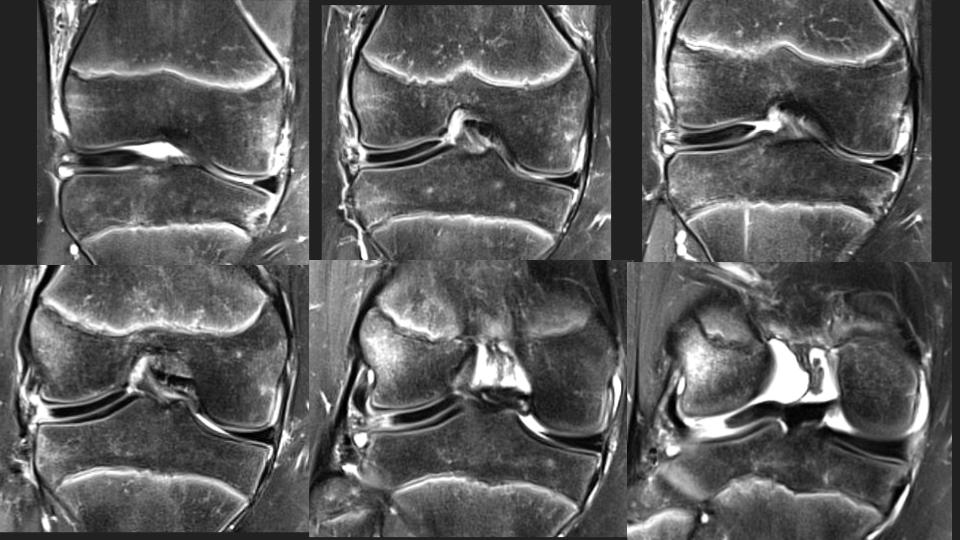

There is an anteriorly flipped bucket-handle type tear of a discoid lateral meniscus, which is not so interesting, until you see the prior MRI 16 months ago. At that time it appears that there was medial displacement of the posterior portion of the discoid LM, with thick irregular linear structures adjacent to the posterior horn region that I think were torn popliteomeniscal fascicles. Perhaps that predisposed to the current injury. The alternative possilbility is that this is a hypermobile discoid lateral meniscus, perhaps a Wrisberg variant. What do you think? Reference article.

discoid lateral meniscus ( RID2771 )